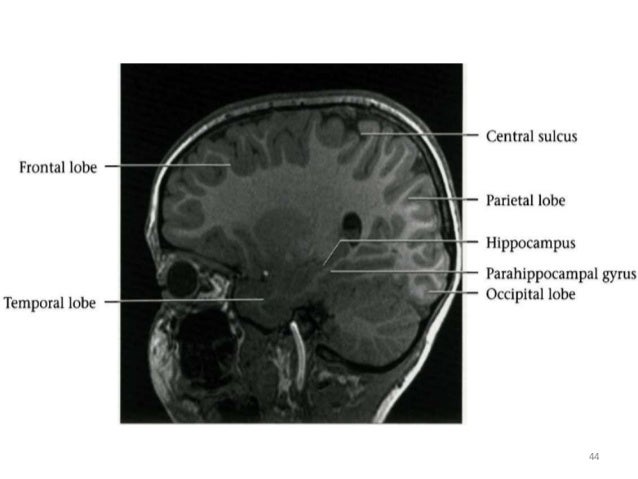

Normal anatomy of brain on CT and MRI

Basic radiological anatomy of the brain and spine with annotated ct and mri images covering the brain, including the brainstem structures and ventricles, and whole spine. The brain receives information through our five senses: This mri brain cross sectional anatomy tool is absolutely free to use.

This mri brain cross sectional anatomy tool is absolutely free to use. It contains information about the normal anatomy and the different types of brain hemorrhage. Essentially normal brain mri for reference. Operculization ,gyri and sulcal development.